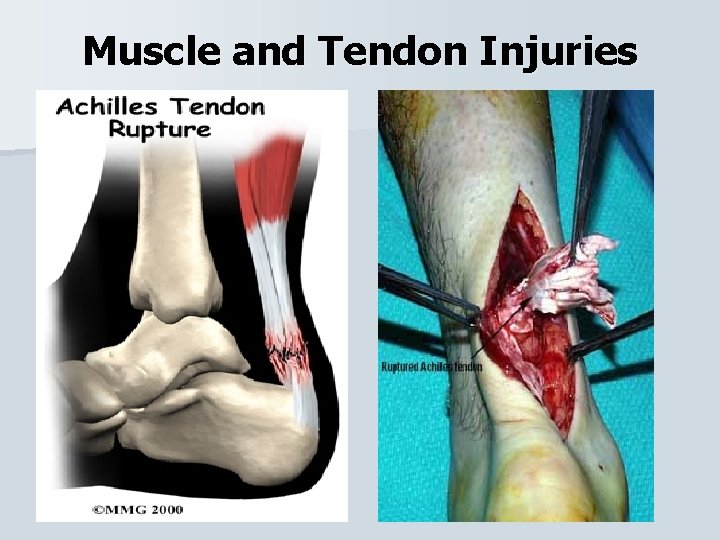

Muscle and Tendon Injuries

Muscle and Tendon Injuries Achilles Tendon Rupture The rupture occurs when the ankle is forced into dorsiflexion, a blow to the back of the leg, or a sudden forceful contraction. • The athlete will have difficulty walking, weakness, and a loss of function (plantarfelxion). There will be swelling and an obvious depression over the tendon attachment. •